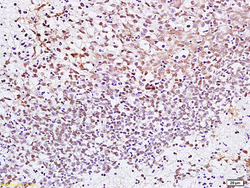

- Main image

- Experimental details

- Formalin-fixed and paraffin embedded human gastric carcinoma labeled with Anti CENPF Polyclonal Antibody, Unconjugated (bs-7839R) at 1:200 followed by conjugation to the secondary antibody and DAB staining.

- Sample type

- Human

- Other comments

- Stomach